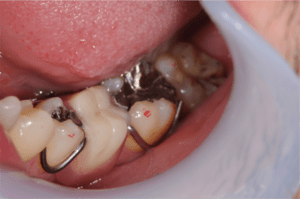

C4状態の虫歯症例の口腔内写真

C4の歯を抜歯後入れ歯をセットした症例の口腔内写真